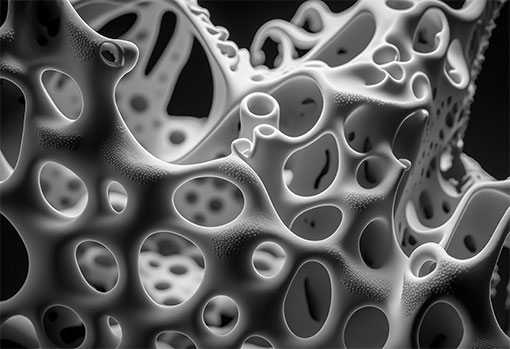

Your bones have two components to them:

These are the proteins (like collagen) that act as reinforcing rods for the bones. They hold the bone framework together.

These are all the minerals that act like wet cement, eventually hardening around the reinforcing rods.

You can’t have “fracture-proof” bones without enough of both components! And you can’t get back the components you’re losing if you aren’t consistently replacing them.